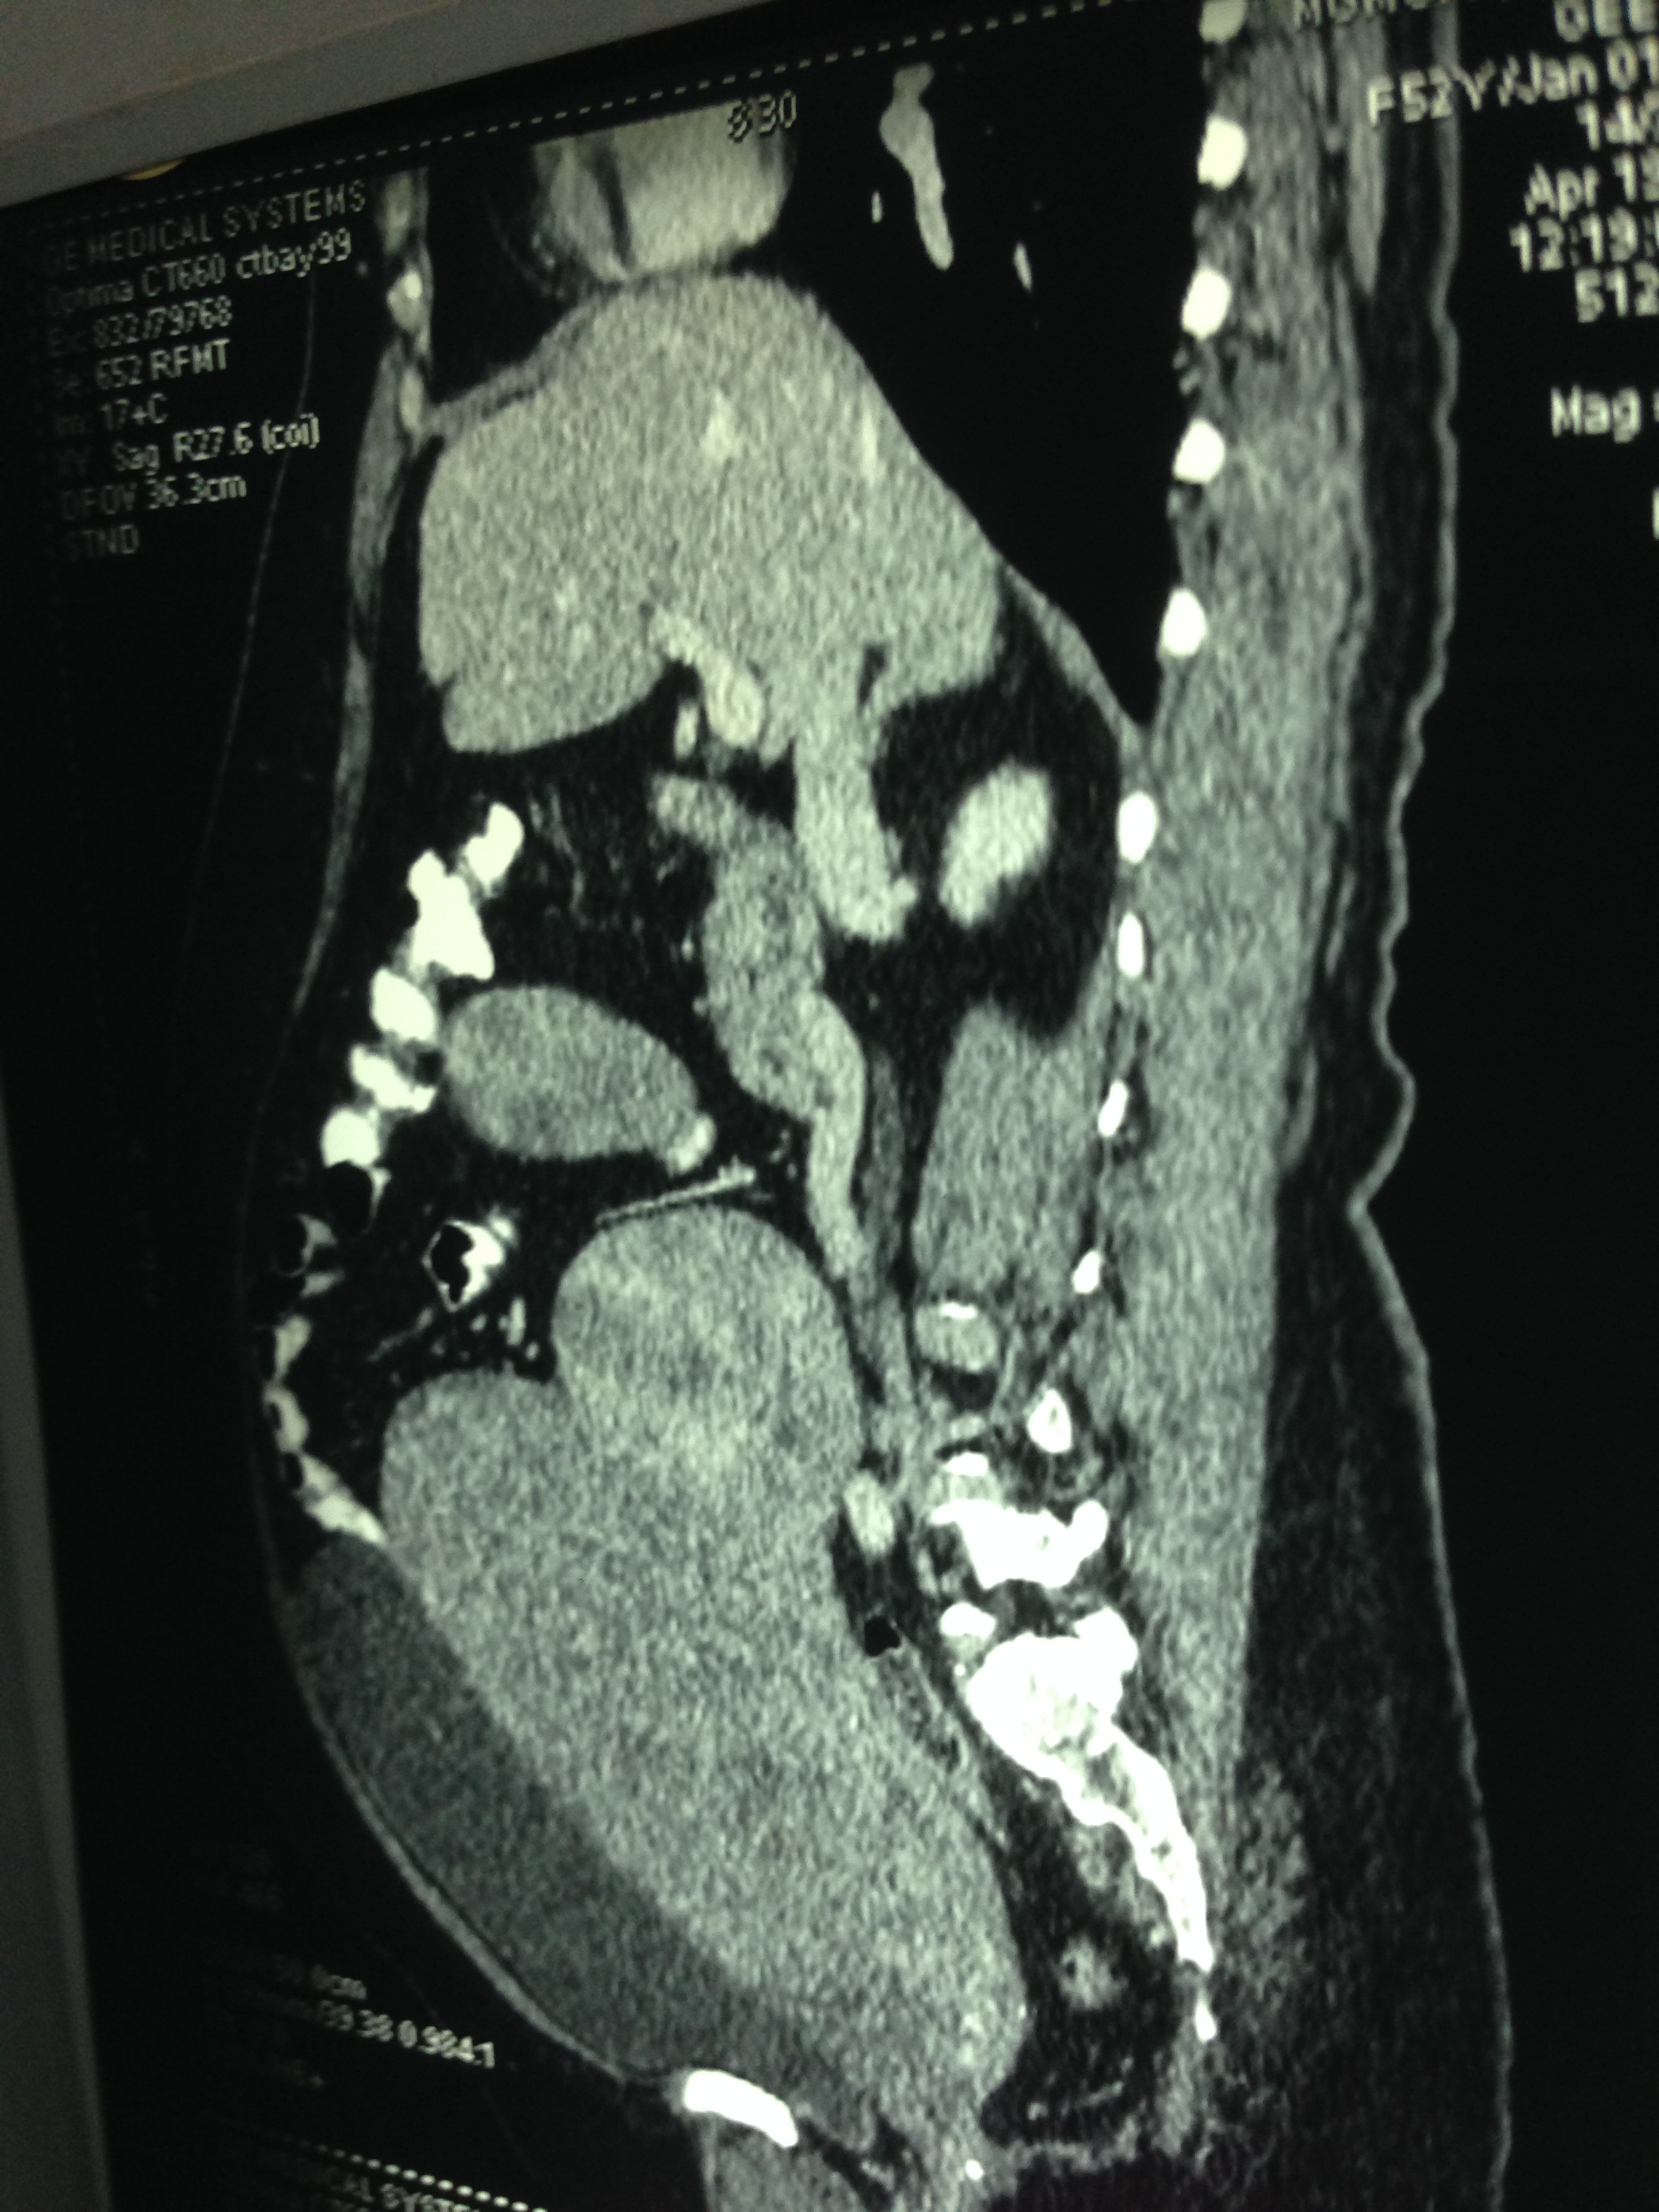

So a CT scan was done next . These pictures are reproduced here using a cell phone’s camera.

The following picture shows the enlarged uterus and large sub serous myomas extending upto the liver.

The next picture shows the adenomyosis

The large sub serous fibroids are seen below.